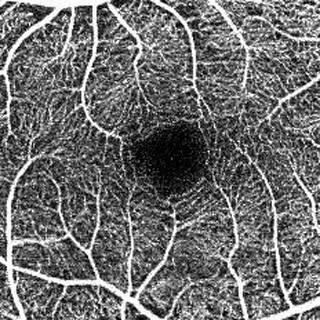

OCT Angiographyは、光干渉断層計で取得した網膜の断層画像から血流情報のみを抽出し、血管像を再構築することで眼底の血管形態を描出する画像処理技術。造影剤を使用しないため、アレルギー反応を引き起こすリスクを伴わずに、網膜や脈絡膜血管内の血流の状態を可視化できる。

OCT Angiographyの画像は、毎秒約7万本の高速スキャンにより最短約3秒の検査時間で取得できるため、被検者の負担を軽くすることに加え、目が動くことによる画像への影響が軽減され、高精細な画像を得ることができる。また、縦分解能3μmという解像度により、網膜血管網を高画質に3D表示でき、立体情報の把握が可能となっている。